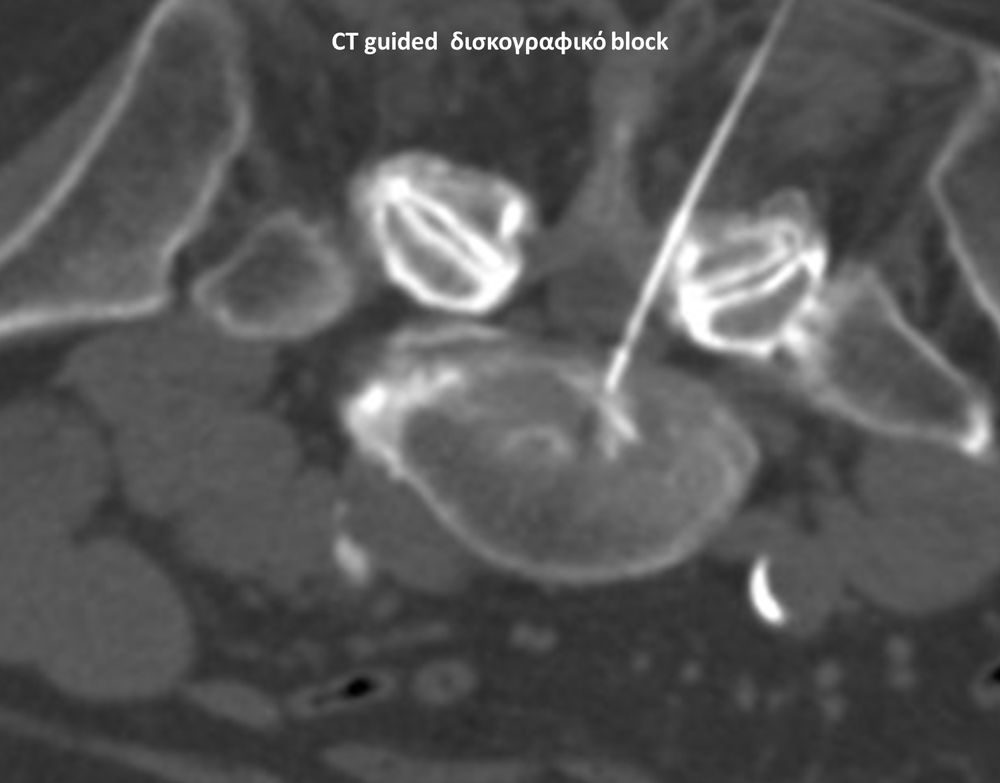

Με την βοήθεια της επεμβατικής ακτινολογίας είναι δυνατόν να πραγματοποιηθούν διαφορες ενέσιμες τεχνικές που αποσκοπούν στη μείωση του μυοσκελετικού πόνου, την ενίσχυση της αποτελεσματικότητας της φυσιοθεραπείας και την επιτάχυνση της διαδικασίας επούλωσης. Οι τεχνικές αυτές περιλαμβάνουν την κατευθυνόμενη έγχυση φαρμάκων ή πραγματοποίηση θεραπευτικών χειρισμών ακριβώς στη θέση τηςπαθολογία. Ετσι εξασφαλιζεται η μέγιστη αποτελεσματικότητα ( έως 95% κατά περίπτωση) και ασφάλεια σε σχέση με τυφλούς χειρισμούς χωρίς ακτινολογική καθοδήγηση.